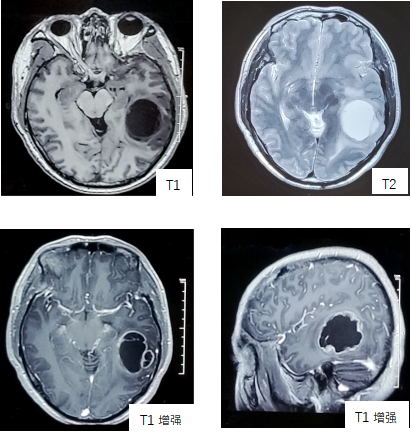

Info: 主诉:记忆力下降3月,语言表达困难1月 病史:50岁男性,3月前家属发现患者出现记忆力下降,反应稍迟钝。近1月来出现语言表达不清、书写困难,并逐渐加重。无恶心、呕吐,无双侧肢体无力,无发作性抽搐,无视力下降。 在当地医院行头颅MRI显示左颞叶占位性病变,囊性,边缘强化明显。 既往史:40年来,左耳中耳炎反复发作,发作时给与滴耳液治疗;3年前诊断为类风湿性关节炎,使用阿达木单抗、来氟米特、甲氨蝶呤等药物治疗。 查体:意识清醒,精神状态良好,情感反应正常,定时定向准确,记忆力良好,语言正常,双侧瞳孔正大等圆,对光反射灵敏。双侧肌力、肌张力未见异常,双侧腱反射正常,双侧巴氏征阴性。 影像学(MR):左侧颞叶界清囊性占位影,T1为低信号伴环形强化,T2呈高信号,囊壁薄、均匀,可见强化,中线脑组织向右有偏移。 术中所见:肿瘤灰白质韧,瘤组织局部囊变,内含囊液。

Sample: 左颞叶病变